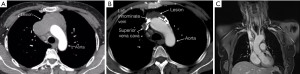

A 57-year-old female patient was admitted to Shanghai Chest Hospital in November 2020 with an anterior mediastinal mass after a B2 thymoma resection 8 years before. Chest computed tomography (CT) revealed an 84mm right anterior mass invading the right lung, bilateral innominate veins, and SVC, with tumor embolism inside the SVC (Figure 1A). Core needle biopsy suggested recurrence of B2 thymoma. After sequential chemoradiotherapy (SCRT), the patient had partial response (PR) and CT revealed the tumor still invaded the right lung, bilateral innominate veins, and SVC, but tumor embolism was not obvious (Figure 1B). The left superior intercostal vein ran down the left side of the aortic arch from the left innominate vein to the azygos vein (Figure 1). The azygos was not invaded by the tumor.

The patient underwent median sternotomy with preparation for SVC reconstruction in April 2021. A right internal jugular vein catheter was placed to monitor IJVP. A radial arterial line was inserted to monitor the systemic blood pressure during surgery. The mass invaded the right upper lobe, bilateral innominate veins and SVC. The enlarged left superior intercostal vein originated from left innominate vein and descended along the left lateral side of aortic arch and joined the azygos vein (Figure 2A). IJVP was found to be 29 cmH2O after clamping the SVC. The tumor and the invaded structures were removed without SVC reconstruction and the azygos vein was reserved (Figure 2B). No obstructive complications were found postoperatively. Operation time was 167 minutes and blood loss was 1,000 mL. The patient started to ambulate on the 2nd postoperative day and was discharged 8 days after surgery. Pathological examination showed mixed thymic carcinoma with 20% thymic squamous cell carcinoma and 80% B2 thymoma. The tumor invaded pericardium, lung, SVC and bilateral innominate veins.

Collateral circulations may develop after chronic SVC obstruction (11). In case 1, preoperative imaging showed that the patients had an obvious collateral vein on the left side of the aortic arch originating from the left innominate vein but it was hard to know if the collateral circulations could completely compensate for the loss of the SVC-innominate vein route. So, we prepared for venous reconstruction before surgery and used intraoperative IJVP to decide whether to perform the reconstruction. We also found a thick collateral vein (left superior intercostal vein) consistent with the imaging intraoperatively (Figure 2B). IJVP was below 30 cmH2O when clamping the SVC, supposing adequate blood return to the heart. Therefore, SVC and bilateral innominate veins were resected without venous reconstruction, while azygos vein were reserved. In case 2, the tumor invaded inside the SVC and azygos vein was also invaded. When clamping the SVC and azygos vein, IJVP was also below 30 cmH2O and therefore SVC, bilateral innominate veins and azygos vein were resected without venous reconstruction. These patients recovered well postoperatively without severe obstructive complications. Long-term follow-up showed more abundant collateral circulations and no recurrence of tumor.